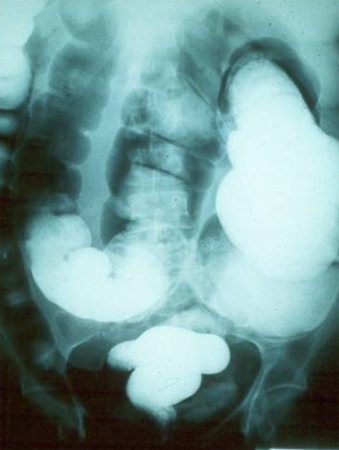

Barium enema showing excessive dilation of sigmoid colon

Grupo de Estudo em Correlalacao Anatomo-Clinica, Clínica Médica, Pontificia Universidade Catolica de Campinas, Sao Paulo, Brazil; used with permission